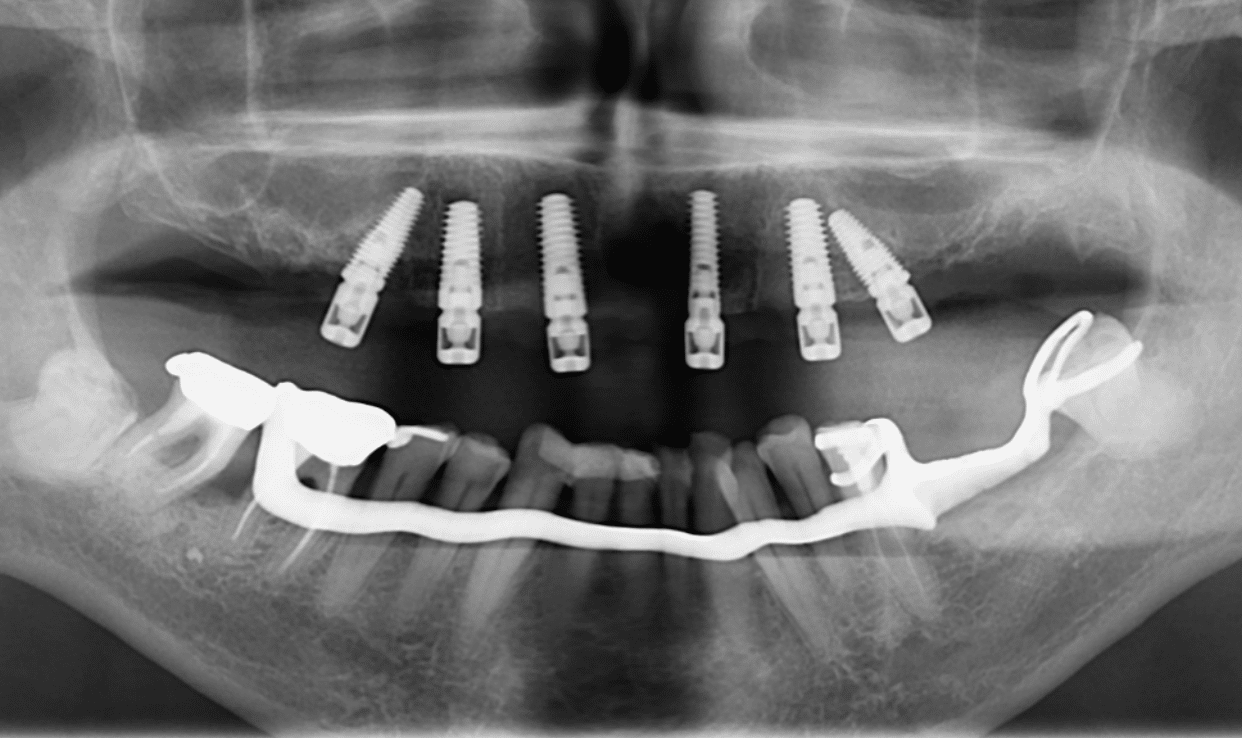

Radio de contrôle post-opératoire (les alvéoles ont été comblées par os autogène et BioOs) :

Notez que l’axe des implants distaux a permis d’éviter les sinus pour une simplification du protocole chirurgical